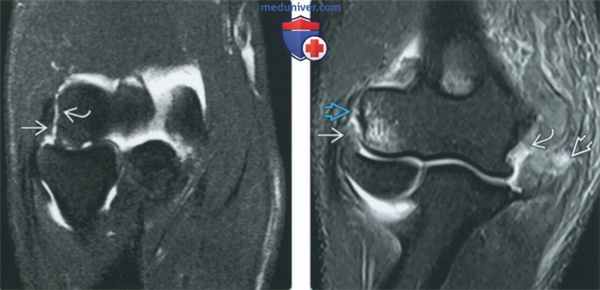

(Слева) МР-артрография в режиме Т2ВИ FSE FS, коронарный срез: визуализируются дегенеративный разрыв ЛуКС и отрыв сухожилия разгибателя вследствие выраженного эпикондили-та.

(Справа) МР-артрография в режиме Т2ВИ FS, коронарный срез: отмечаются поел едав и я вывиха - разрыв лучевой и локтевой коллатеральных связок, а также сухожилий разгибателей и сгибателей в месте их отхождения.